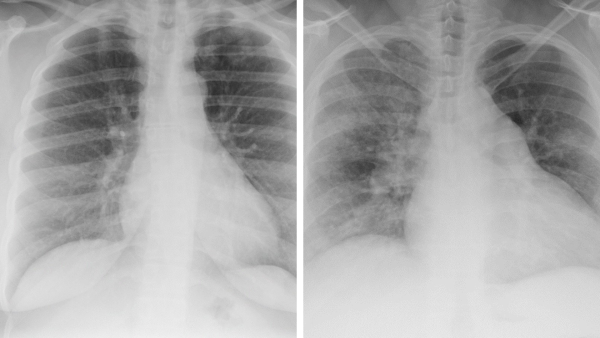

(Left) How a hairstyle of thick cornrows braided down presents on a chest x-ray; (right) how large braids present on a chest x-ray.

As Dr. Maresky explains, that’s a real problem. “Radiology is still a largely white profession, and many of us are biased in our thinking about what ‘normal hair’ should look like on radiologic imaging,” he says. “If an x-ray shows anything over the upper chest other than Caucasian hair, our first instinct is often that it’s abnormal, which can lead to a whole host of different—and incorrect—diagnoses.”

For example, a radiologist might decide that "locs" —which appear as a series of wavy lines on an x-ray—are evidence of tuberculosis or pneumothorax: two diagnoses that require serious, and potentially life-changing, treatment.